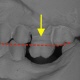

Mit den Zähnen ist es so ähnlich wie mit den Gliedern in einer Kette. Jeder Zahn ist von seiner Architektur her perfekt auf seine jeweilige Aufgabe aufgebaut. Doch das System funktioniert nur so gut wie das sprichwörtlich schwächste Glied in der Kette. Der Verlust nur eines einzelnen Zahnes bedingt, dass eine unterbrochene Zahnreihe entsteht und das Zusammenarbeiten der Zähne gestört ist. In aller Regel entsteht ein so genanntes instabiles System. Das bedeutet, dass der Zahnverlust zwangsläufig zu negativen Veränderungen führt.

Zahnlücken sind nicht nur äshtetisch negativ

...sondern haben zahlreiche ungünstige Auswirkungen.